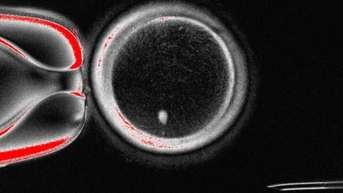

Chị Ngọc hạnh phúc khi đón con yêu khỏe mạnh sau 3 lần sẩy thai vì mang gene bệnh hiếm - Ảnh: D.LIỄU

អ្នកស្រី ង៉ុក រីករាយស្វាគមន៍ទារកដែលមានសុខភាពល្អ បន្ទាប់ពីរលូតកូនបាន ៣ ដង ដោយសារមានជម្ងឺហ្សែនដ៏កម្រ - រូបថត៖ D.LIEU

នៅឆ្នាំ 2022 ង៉ុកបានសម្រេចចិត្តព្យាយាមម្តងទៀត ហើយបានទៅមន្ទីរពេទ្យដើម្បីពិនិត្យសុខភាព។ នៅពេលនោះ គ្រូពេទ្យបាននិយាយថា ទាំងប្តី និងប្រពន្ធបានផ្ទុកហ្សែន ថាឡាសស៊ីមី ដែលជាមូលហេតុដែលនាំឱ្យនាងរលូតកូនចំនួនបីដង។

លោក Dung បាននិយាយថា នៅពេលនោះ វេជ្ជបណ្ឌិតបានផ្តល់ដំបូន្មានថា មានឱកាសតែ 25% ប៉ុណ្ណោះក្នុងការមានកូនដោយគ្មានហ្សែន ហើយ IVF រួមជាមួយនឹងការពិនិត្យអំប្រ៊ីយ៉ុងអាចប្រើដើម្បីបង្កើតអំប្រ៊ីយ៉ុងដែលមានសុខភាពល្អ។ ពេល​នោះ​ក្តី​សង្ឃឹម​មួយ​បាន​ភ្លឺ​សម្រាប់​គូស្នេហ៍ ប៉ុន្តែ​ថ្លៃ​ចំណាយ​ខ្ពស់​ពេក ហើយ​ប្តី​ប្រពន្ធ​មិន​មាន​លុយ​គ្រប់​គ្រាន់។

ជាសំណាងល្អ ក្នុងឆ្នាំ 2023 ពួកគេបានទទួលកញ្ចប់ជំនួយ IVF ដោយឥតគិតថ្លៃ ហើយមានផ្ទៃពោះជាលើកដំបូងដោយជោគជ័យ។ នៅខែសីហាឆ្នាំ 2023 ប្តីប្រពន្ធនេះបានស្វាគមន៍ទារករបស់ពួកគេ។